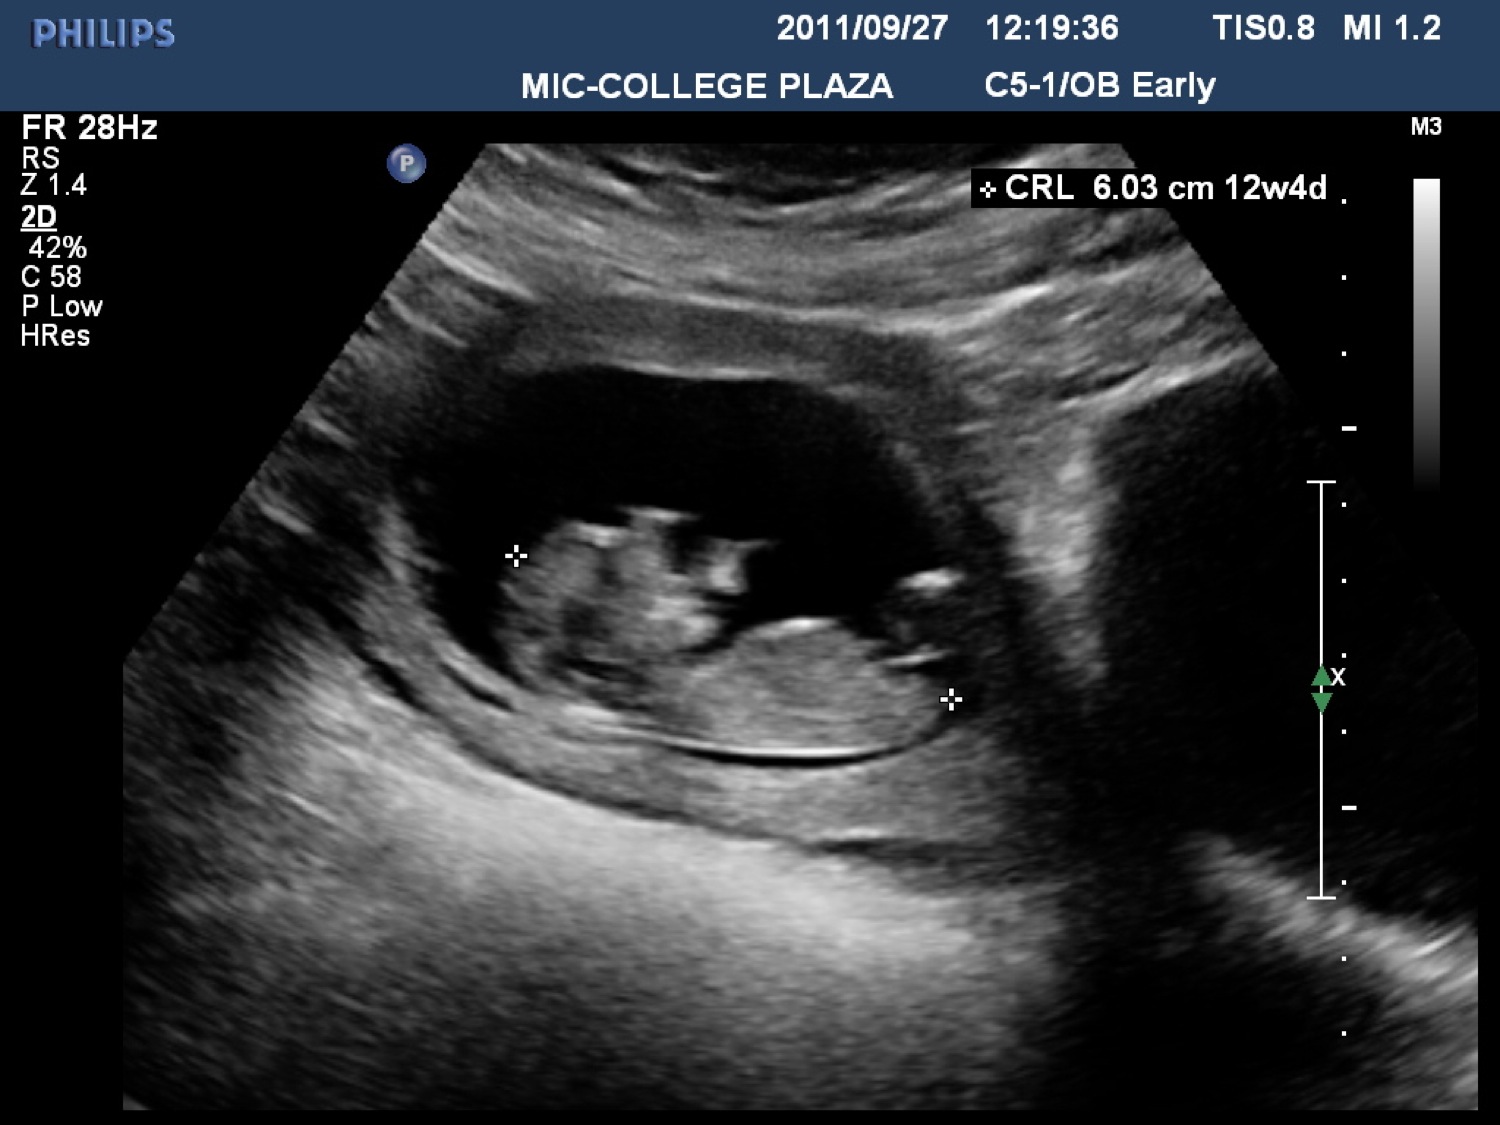

We had an ultrasound today and June was having a ball trying to pin down our lil steam roller to get a measurement! I guess it was more into rolling and turning than letting her do her job! We were able to get a measurement of 12 weeks, 4 days - and today we are 12 weeks, 3 days pregnant --- so pretty bang on! The heartbeat was a healthy 170 bpm.